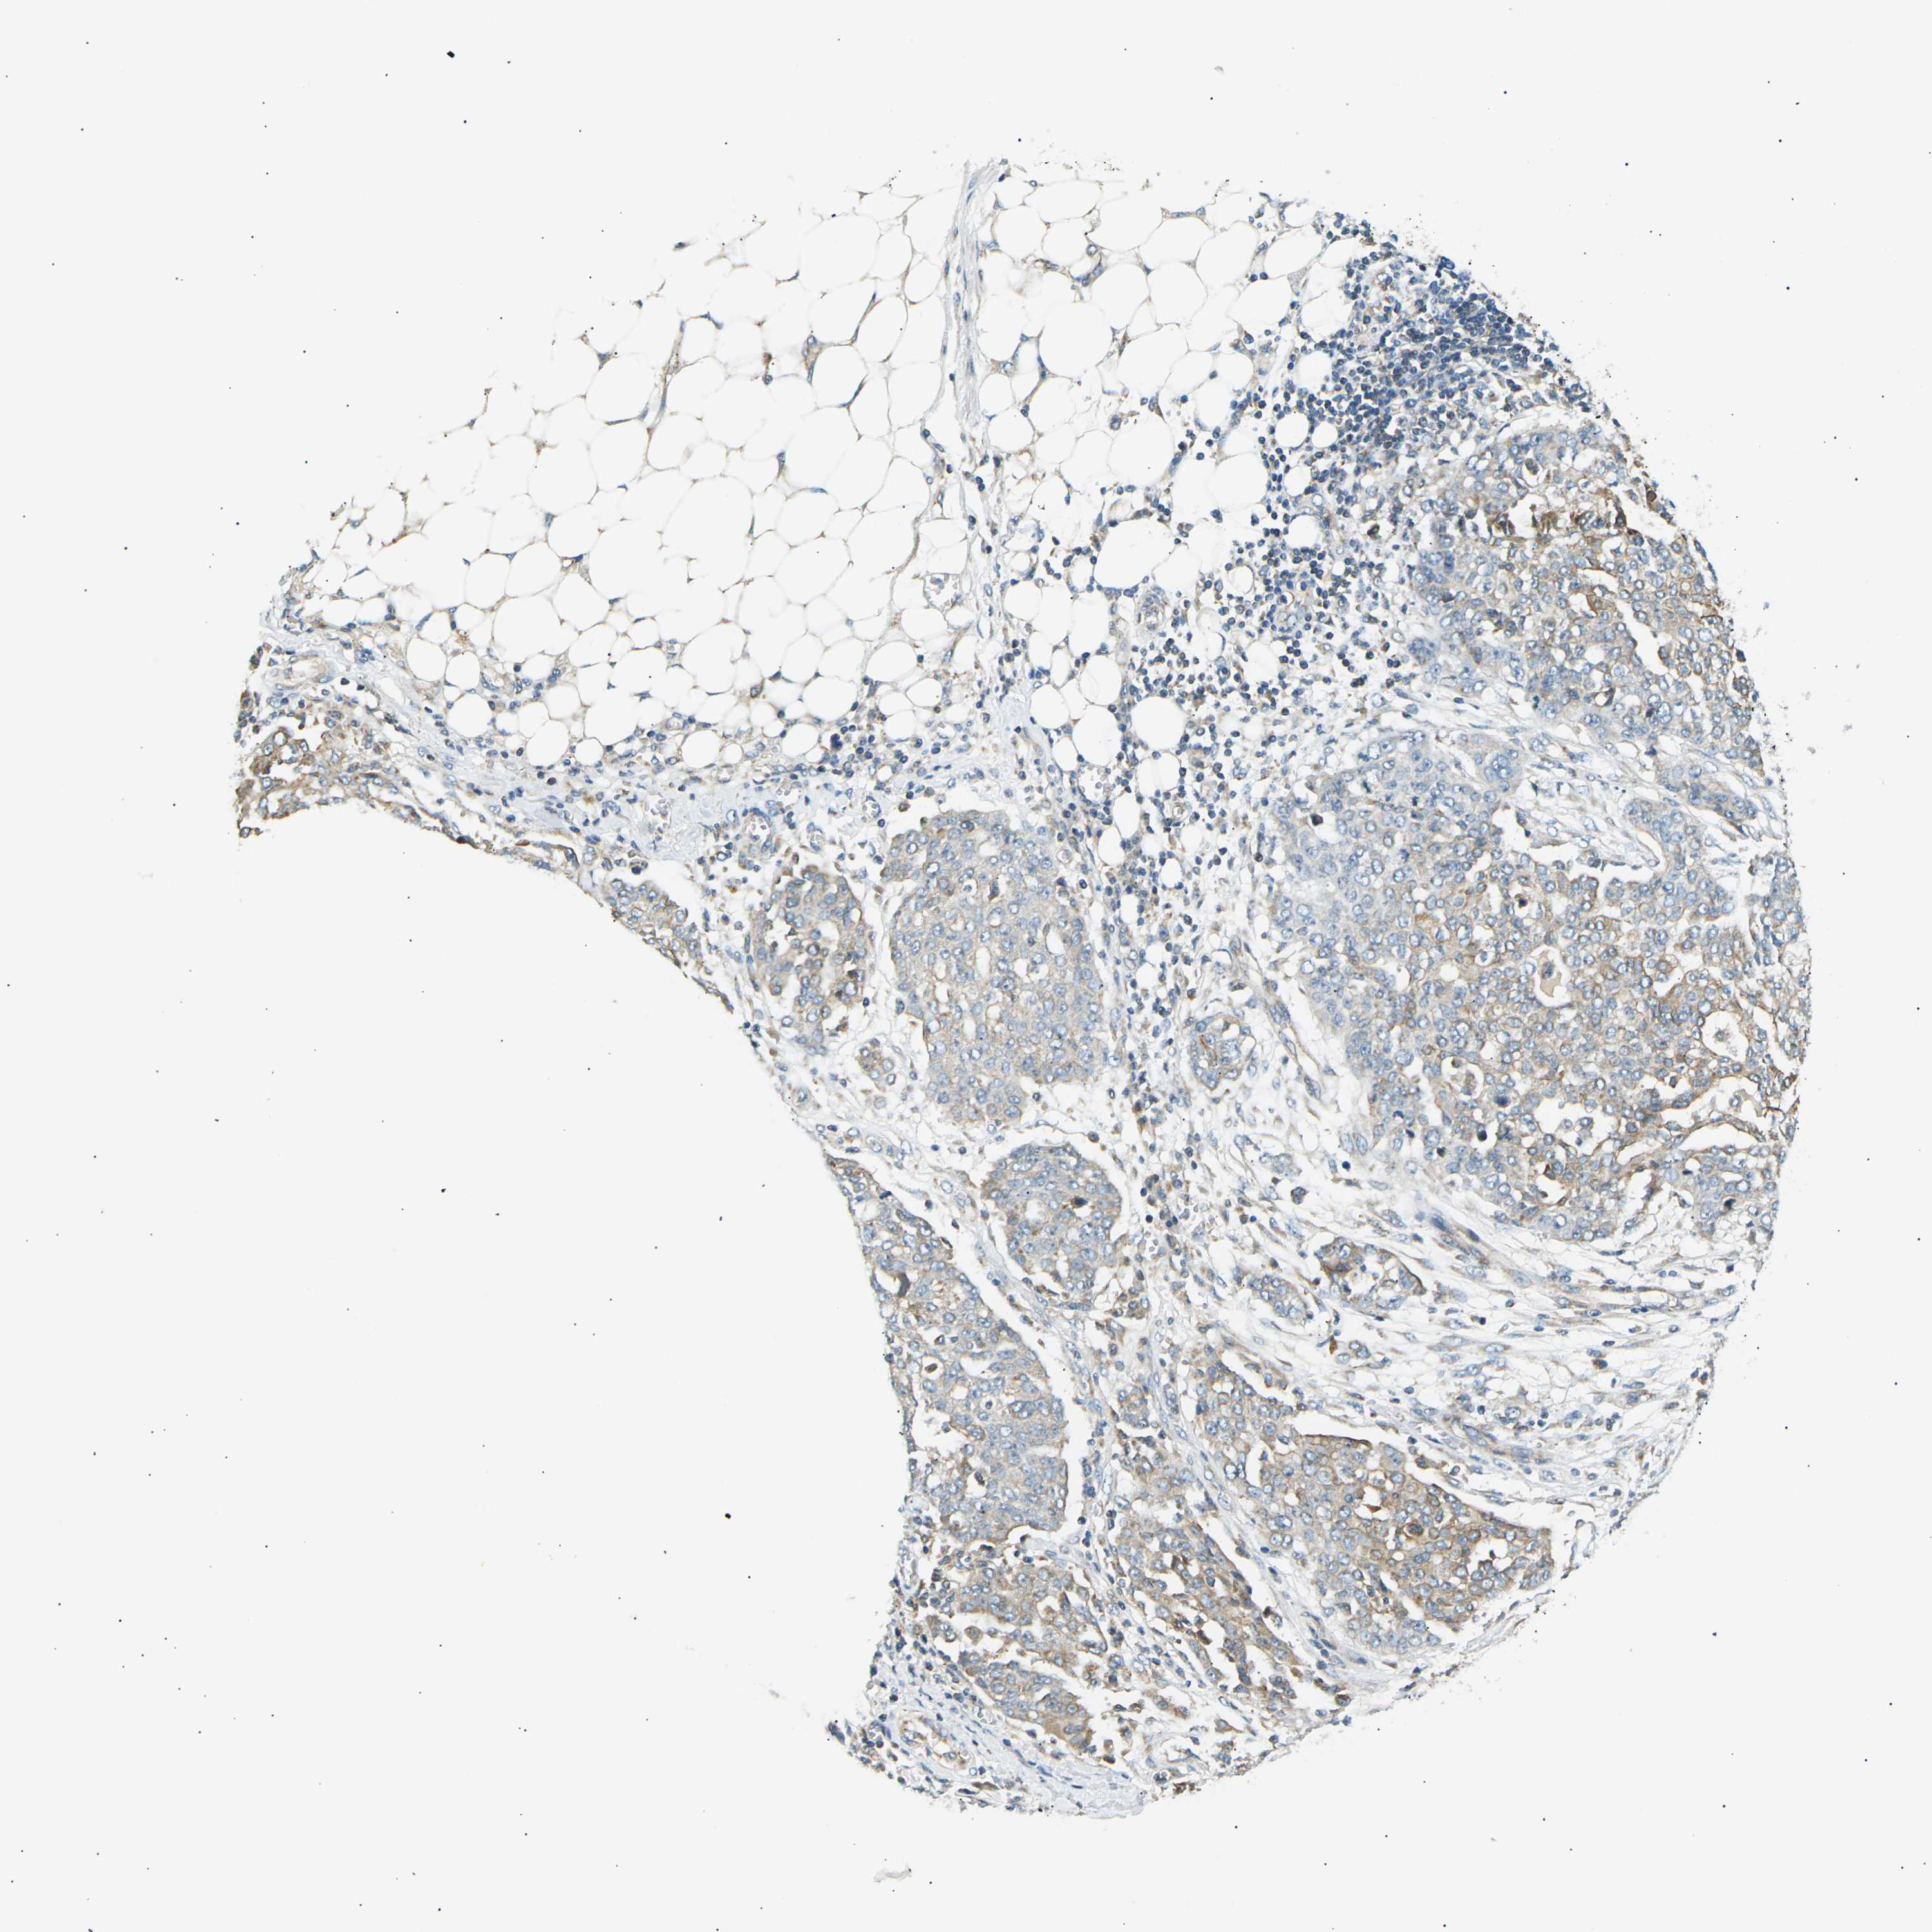

OVARIAN CANCER - Protein expressioni

A mouse-over function shows sample information and annotation data. Click on an image to view it in a full screen mode. Samples can be filtered based on level of antibody staining by selecting one or several of the following categories: high, medium, low and not detected. The assay and annotation is described here.

Note that samples used for immunohistochemistry by the Human Protein Atlas do not correspond to samples in the TCGA dataset.

Antibody stainingi

Antibody staining in the annotated cell types in the current human tissue is reported as not detected, low, medium, or high, based on conventional immunohistochemistry profiling in selected tissues. This score is based on the combination of the staining intensity and fraction of stained cells.

Each image is clickable and will lead to virtual microscopy that enables deeper exploration of all samples and also displays staining intensity scores, fraction scores and subcellular localization as well as patient and tissue information for each sample.

Antibody CAB015211

Cystadenocarcinoma, serous, NOS

Carcinoma, endometroid

Cystadenocarcinoma, mucinous, NOS

Carcinoma, NOS